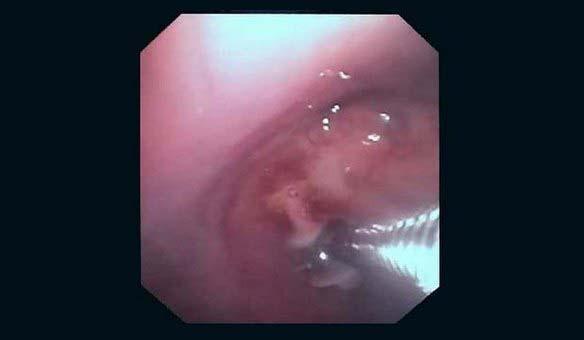

Вчера в отделении эндоскопии успешно апробировано окклюзия бронхоплеврального свища.

Пациент К. 1960 г.р., после правосторонней пульмонэктомии от 2019 г. поступил в отделение многоплановой хирургии. При плановой бронхоскопии выявлена несостоятельность культи правого главного бронха, устье свища до 0.3 см, откуда поступает слизисто-гнойное содержимое. В устье свища определяется сшивающая скоба. Также у пациента имеется дренажная трубка справа в 7 межреберье, подключаемая к активному отсосу.

Во время повторной бронхоскопии под интубационным наркозом установлен окклюдер из ИМН другого назначения (PULL THRU) в устье свища. Поперечные резиновые лепестки на окклюдере и скоба в устье свища должны надёжно фиксировать положение окклюдера.

Оборудование: видеобронхоскоп Olympus 180, окклюдер PULL THRU( Medivators)